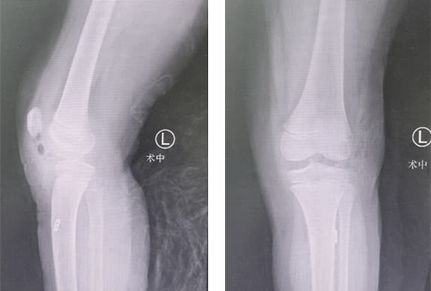

术后

经过团队共同努力,手术顺利完成。术后表面仅留下0.5厘米的两个小口,而术中出血量也仅有10ml。

张传开主任介绍:关节镜微创手术对于患者来说,创伤小、恢复快,且术中出血量少。最重要的是,术后手术部位的疼痛感,较之传统手术要小很多,这对年龄较小的患者来说是非常关键的。